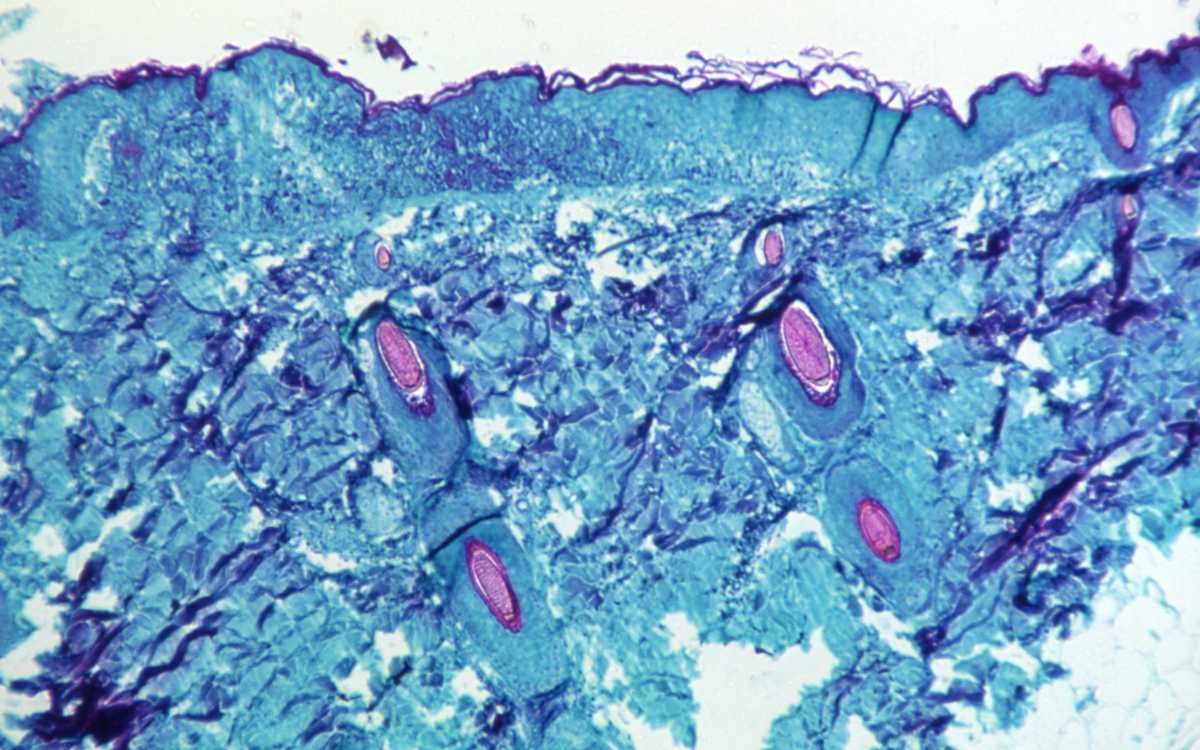

La OMS se reúne para determinar el nivel de riesgo “moderado” o de emergencia de la viruela del mono

GINEBRA – El Comité de Emergencia de la Organización Mundial de la Salud (OMS) se reúne este jueves para analizar el brote de viruela del mono en países no endémicos y determinar si se mantiene el nivel de riesgo “moderado” que se le ha asignado o debe ser declarado una emergencia sanitaria internacional, como el…

Viruela del mono representa ‘riesgo moderado’ para la salud pública mundial: OMS

“El riesgo para la salud pública podría llegar a ser alto si este virus aprovecha la oportunidad de establecerse como patógeno humano y se extiende a grupos con mayor riesgo de padecer enfermedades graves, como los niños pequeños y las personas inmunodeprimidas”, dijo la OMS. Hasta el 26 de mayo se han notificado 257 casos…